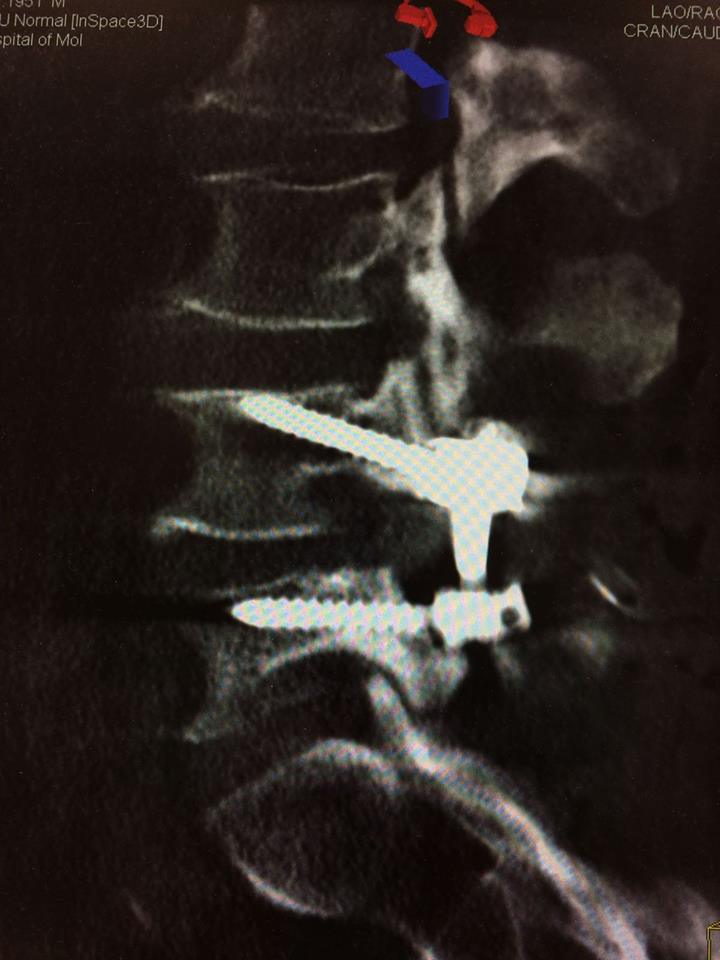

Echipa de specialiști în neurochirurgie spinală a Spitalului Clinic Republican a obținut o nouă realizare. S-a reușit o fuziune intervertebrală cu șuruburi transpediculare și cușcă intervertebrală printr-o incizie mai mică a pielii, de doar 4 cm, recordul anterior fiind de 5 cm. Succesul intervenției se datorează folosirii tehnologiilor moderne (CT intraoperatorie, Neuronavigația spinală, Neuromonitoring intraoperator) și planificării preoperatorii detaliate.

Pentru tratarea unui pacient de 63 ani cu diagnosticul de Spondilolistezis instabil L4-5, însoțit de stenoză de canal lombar, a fost folosit un abord chirurgical nou - Fuziunea Intervertebrală Mediană.

Intervenția chirurgicală de acest gen presupune o incizie mai scurtă, mobilizare limitată a țesuturilor și, respectiv, o hemoragie redusă. Durerea postoperatorie este mai mică, iar reabilitarea are loc mai rapid.